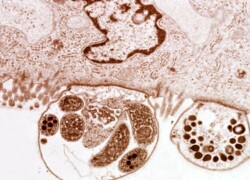

IBD (inclusion body disease) jest ciężką, nieuleczalną chorobą węży. Szczególnie zagrożone są węże z…

Po raz pierwszy zostały one opisane w 1907 roku przez Ernesta E. Tizzer’a (2,…